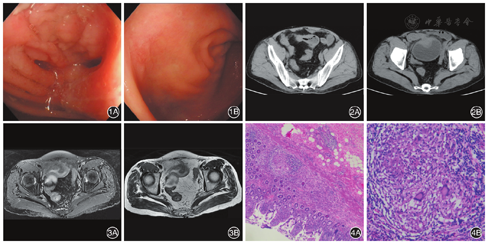

患者女,58岁,因"反复腹痛8年,加重伴浑浊尿2个月余"于2017年4月5日入院。患者腹痛主要为下腹部,位置稍偏右,呈隐痛,伴大便次数增多,2~4次/d,间断有黏液便。曾于当地行肠镜提示"回肠末端及大肠溃疡性炎症",服用美沙拉嗪肠溶片,症状一度好转,但2014年起停药,期间出现腹痛。2017年2月患者发现尿液颜色加深,有杂质,外观浑浊,伴尿频、尿急、排尿不尽感及轻微尿痛。既往有子宫肌瘤行全子宫切除病史。入院体检:腹软,下腹正中部位轻度压痛,无反跳痛,腹部未触及包块,移动性浊音阴性,肠鸣音4次/min。血常规示血红蛋白103 g/L,红细胞压积0.316。尿常规示白细胞反应(++),白细胞158.10/μL。尿液涂片:革兰阳性球菌呈中量(+++),真菌孢子呈中量(+++),革兰阴性杆菌少见(+)。骨髓涂片:骨髓增生极度减少,以红系和巨核细胞减少为主。骨髓活检:骨髓增生较低下,脂肪约占髓腔面积的75%,粒红比例大致正常,粒红系均以中晚幼阶段细胞为主;Ag(-),Fe(-)。当次住院肠镜示回肠末端肠腔管壁增厚,黏膜水肿呈结节样,管腔狭窄,从狭窄处至回盲瓣回肠段见散在数个少苔溃疡,并见瘢痕形成,致肠腔变形(图1A);回盲瓣变形,并见一薄苔溃疡,周边黏膜皱缩,0.4 cm×0.5 cm;盲肠见两个浅表小糜烂灶;全结肠黏膜散在充血水肿,直肠近端见散在多个浅表不规则溃疡,大小不等,并见一肉芽组织样小隆起(图1B)。病理检查示回肠末端黏膜慢性炎,回盲瓣呈慢性炎伴炎性渗出、坏死,且伴肉芽组织形成,符合克罗恩病(Crohn disease,CD)的典型表现。CT示回肠远段改变,考虑炎症性肠病可能性大,肠壁穿孔并累及膀胱;子宫未见显示(图2)。MRI示回肠远段肠壁增厚、穿孔并内瘘形成,考虑CD可能性大,形成炎性肿块累及膀胱前上壁;子宫缺如(图3)。2017年4月15日经首次多学科团队(MDT)讨论,认为病理未见干酪样坏死,且患者缺乏全身中毒症状,初步排除结核;综合患者的病史、腹部影像学及病理学检查,诊断其为"CD并回肠-膀胱瘘"的可能性大;由于CD为内科疾病,且患者因停药而导致复发,故可先进行内科保守治疗,建议使用生物制剂英夫利西单抗(infiximab,IFX)治疗,但患者因经济原因拒绝使用;由于骨髓象增生低下,故暂不使用硫唑嘌呤等免疫抑制剂,予美沙拉嗪,辅以调节菌群、保护肠道黏膜及纠正贫血等治疗。患者出院后腹痛有好转,但混浊尿等症状未见明显改善。2017年6月25日再次住院,第2次MDT讨论,认为该患者瘘管口径较大,内科保守治疗不理想,且存在骨髓抑制,免疫抑制剂的使用受限,因此具有手术适应证,遂于6月29日在全麻下行"回肠部分切除术+膀胱部分切除术+回盲部切除术"。术后病理:小肠及大肠黏膜呈慢性活动性炎症改变,炎症节段性加重,局灶炎症穿透肠壁全层,肌层坏死断裂,肉芽组织增生,呈裂隙状溃疡改变;固有层内多灶类上皮细胞增生形成肉芽肿,未见凝固性坏死(图4),符合CD表现。术后患者浑浊尿消失,偶有中腹痛。术后10 d余,患者腹部切口有红肿及渗液,腹部查体无压痛及反跳痛,肠鸣音正常。考虑为手术后伤口愈合不良,予伤口清创及抗生素预防感染。1周后患者切口愈合良好,腹痛明显缓解,偶有中腹胀,无浑浊尿,嘱门诊随访。目前予硫唑嘌呤50 mg(每日1次)、美沙拉嗪缓释颗粒1.0 g(每日4次)维持缓解。患者体重由术前42 kg上升至51 kg,红细胞沉降率由术前102 mm/h下降至16 mm/h,C-反应蛋白由21.2 mg/L上升至4.1 mg/L,血红蛋白由术后的86 g/L上升至98 g/L。